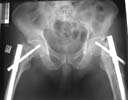

AP Pelvis

Attached here few x-rays of a multi-trauma patient. He is a 51years old man,sustain MVA at 08/15/99 and refer to our hospital few days ago, more than twoweeks after injury. He sustain Bilateral femoral fracture including femoralneck, A right humerus fracture, right distal radius fx, left open ulnar fx,right tibial plateau (type III) fx and Chopart fracture dislocation of the rightfoot. At the other hospital where he was admitted, He underwent laparotomy andfixation of both femur by reconstruction IMN, application of Ex Fix to thehumerus, and reduction and K.W. fixation of the Rt foot. He is currently stable and conscious. He is scheduled next week for replacing of the Rt IMN to aretrograde nail and pinning (6.5 mm screws) of the neck fracture, fixation ofthe ulna, distal radius and tibial plateau.

The implant selection was right but application technique and length of the nail were not. Lateral x-rays of the hip should be taken to confirm reduction of the femoral neck (bilaterally?).

In my opinion both fractures sould be revised with closed interlocking nailing with the same nail, appropriate length using two proximal locking screws to the head. Two screws for distal locking must be also used because these are very unstable fractures.